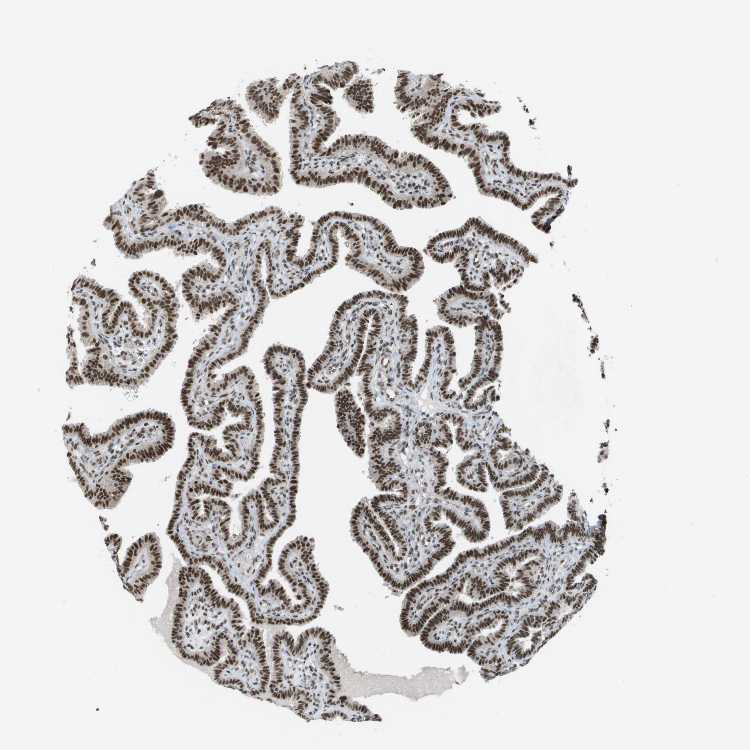

FALLOPIAN TUBE - Antibody stainingi

Antibody staining in the annotated cell types in the current human tissue is reported as not detected, low, medium, or high, based on conventional immunohistochemistry profiling in selected tissues. This score is based on the combination of the staining intensity and fraction of stained cells.

Each image is clickable and will lead to virtual microscopy that enables deeper exploration of all samples and also displays staining intensity scores, fraction scores and subcellular localization as well as patient and tissue information for each sample.

Antibody HPA017224

Glandular cells High